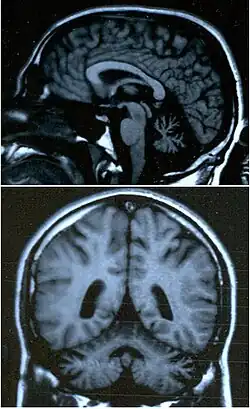

Le cervelet est le centre de la coordination fine des mouvements des muscles, l'information qui en émerge est véhiculée jusqu'aux muscles par la moelle épinière et les nerfs périphériques. Pour cette raison, une atteinte soit de la moelle épinière soit des nerfs périphériques peut causer une ataxie.

- Dans l'ataxie cérébelleuse (atteinte au niveau du cervelet), on retrouve un écartement des pieds (élargissement du polygone de sustentation) ainsi que des oscillations rythmiques des tendons des chevilles (danse des tendons). De plus, on observera une asynergie, des dyschronométries, ainsi qu'une hypermétrie.